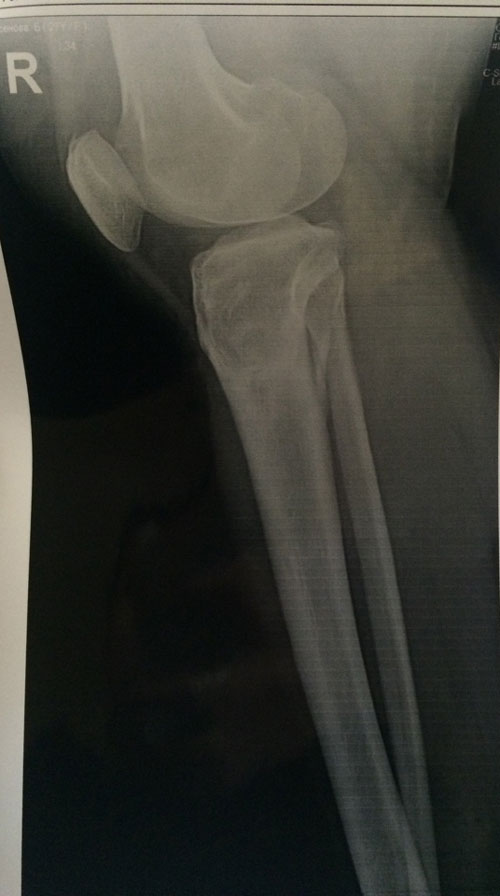

Диагноз: ахондроплазия, варусная деформация обеих голеней 155 градусов.

26 лет.

Дата операции 08.07.2015г.

Исходник.